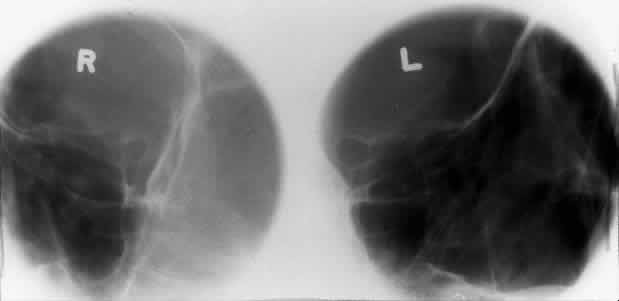

The optic foramen should measure 6 mm vertically and 5 mm horizontally. Asymmetry greater than 1 mm or a vertical dimension greater than 6.5 mm is considered abnormal.15,27 Ninety-eight percent of patients have optic canals that vary by less than 1 mm.27 Concentric enlargement of the foramen and optic canal can be seen with optic nerve gliomas, meningiomas, neurofibromatosis, and less commonly an aneurysm of the ophthalmic artery (Fig. 16). A decrease in the optic foramen and canal dimension can be seen in fibrous dysplasia, Paget's disease, hyperostosis secondary to a meningioma, or microphthalmos (Fig. 17, Table 1).

Fig. 16. Oblique apical projections showing the optic foramen. The left optic foramen has concentric enlargement from an optic nerve glioma. The foramen should not have greater than 1 mm of asymmetry.